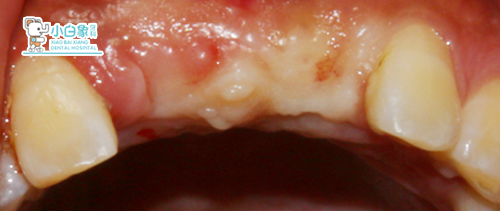

检查:合面部未见异常,口内查:11、21牙槽嵴丰满度尚可,牙龈颜色正常,扪诊未见明显骨质隆突。

X线片+口内像

治疗过程:11、21必兰局麻下切开,翻瓣,拔除11后见颊侧骨板缺失,逐级备洞后21植入3.3*10mm,11植入3.3*11.5mm美格真种植体各一枚,植入Bio-oss骨粉,覆盖海奥膜,严密缝合。